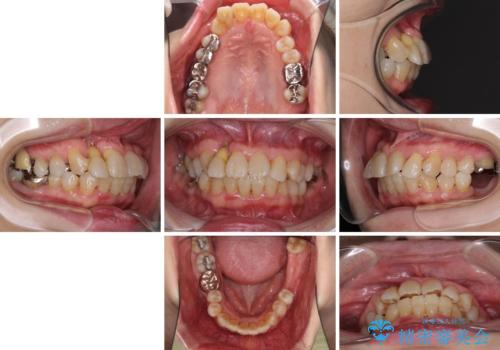

- 歯の欠損や歯肉からの出血などを気にして来院された患者様です。

診査の結果、歯周病であることが分かり、抜歯が必要な歯も見受けられました。

骨造成やインプラント、歯周外科、歯肉移植、矯正など、多くの処置を組み合わせて治療を行うこととしました。